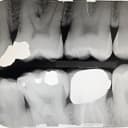

Bitewing (عکس از بین دندانها)